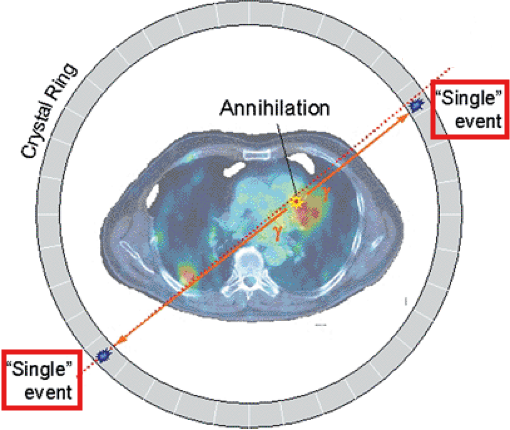

Picks up 2 photons – the photons emitted from an annihilation reaction

What is the relationship between each detector pair inside the ring of detectors in a PET camera?

Each detector works together with the detector opposite to it – allows it to pick up on a line of response

What is a line of response?

When the photons from an annihilation reaction are emitted, they will travel in opposite directions of one another – makes a 180-degree line almost

How does a ‘dot’ from our image translate from the reaction at the PET detectors?

The detectors create a dot on our scanned image from the point at which the 2 photons are overlapping – or where they cross each other in the ring of detectors but we still need more information to specifically determine it!

What is needed in order for the PET detectors to determine where an annihilation reaction occurred on a line of response?

Requires multiple line of responses to figure out where the intersection of where the annihilation reaction took place

Is a line of response able to determine where the photon originated from?

No, it’s only able to determine where the annihilation took place

Cannot tell us where the positron was ejected from as it will travel away from the original nucleus